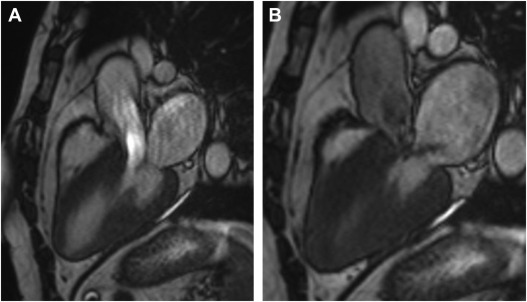

Standardized cardiovascular magnetic resonance imaging (CMR) protocols: 2020 update.

Comparison between three-dimensional navigator-gated whole-heart MRI and two-dimensional cine MRI in quantifying ventricular volumes.

Volumetric cardiac quantification by using 3D dual-phase whole-heart MR imaging.